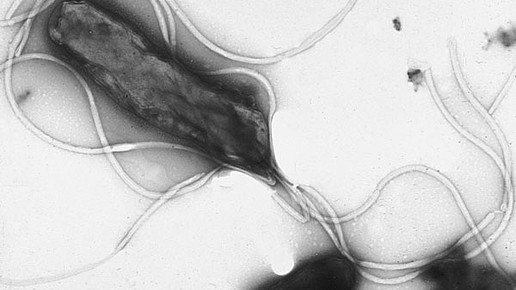

Der Erreger Helicobacter pylori ist dafür bekannt, Magenerkrankungen wie Gastritis hervorzurufen. Im schlimmsten Fall kann die Entzündung zu Magenkrebs führen. Wissenschaftlerinnen der Medizinischen Hochschule Hannover (MHH) haben nun einen der wichtigsten Mechanismen entdeckt, die das Bakterium dafür nutzt.

Bisher ist unter anderem bekannt, dass Helicobacter pylori (H.pylori) über seine Geißeln ein Peptidoglykan ins Innere der Magenepithelzelle injiziert. Dort löst es nach Interaktion mit dem Rezeptor Signalprozesse aus, die dann eine Entzündung der Magenschleimhaut hervorruft. Der Mechanismus ist genetisch codiert, der entsprechende Abschnitt auf dem Bakterienchromosom hat den Namen „cytotoxin-associated genes pathogenicity island“ (cagPAI). Außerdem gibt es unter den zahlreichen H. pylori-Stämmen virulente sowie weniger virulente Formen. In Magen- und Darmulzera werden hauptsächlich zytotoxinbildende Stämme nachgewiesen.

Die Forscherinnen um Professorin Dr. Christine Josenhans vom Institut für Medizinische Mikrobiologie und Krankenhaushygiene entschlüsselten in ihrer aktuellen Studie, welche Strukturen sich hinter der kanzerogenen Wirkung von H.pylori verbergen. Sie konnten zeigen, dass das in die Zelle eingeschleuste Peptidoglykan auf bestimmte Proteine trifft, die proinflammatorische Signale an den Zellkern weiterleiten. Ihre Ergebnisse veröffentlichten sie im Fachjournal „Plos Pathogens“.